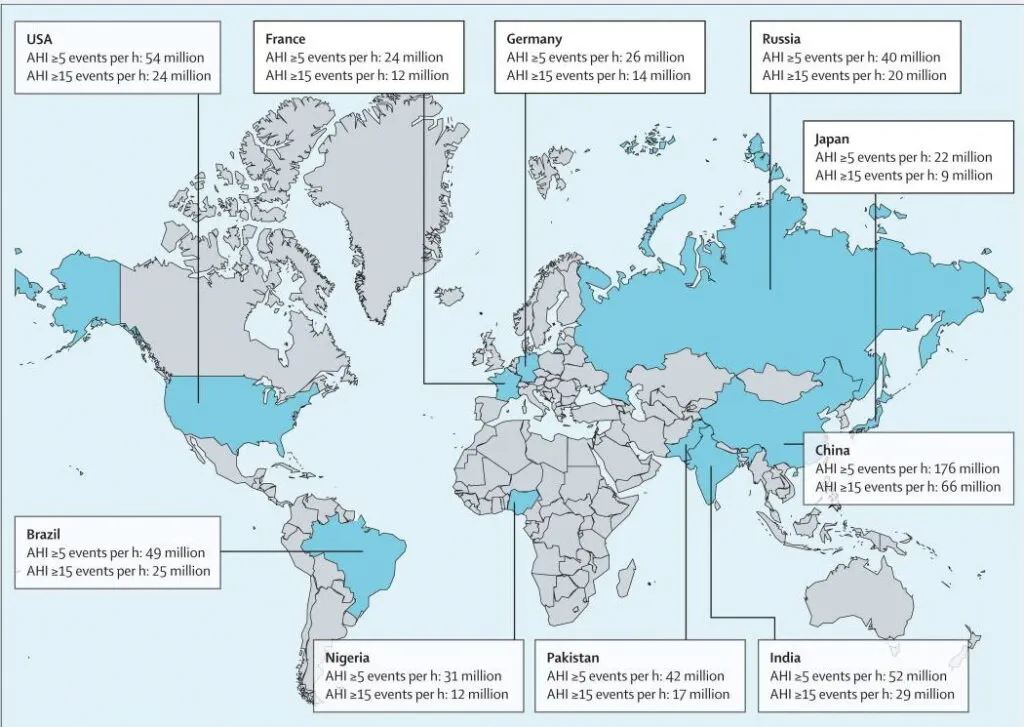

Schlafapnoe-Syndrom - Häufigkeit

Vor 50 Jahren als die ersten Studien zum Schlafapnoe-Syndrom (SAS) veröffentlicht wurden musste man sich die Patienten dafür noch mühsam zusammensuchen. Heute ist es weit verbreitet und wird als fortschreitende, chronische Krankheit angesehen. (1) Die Zahlen, wie viel Menschen (wahrscheinlich) vom Schlafapnoe-Syndrom in Deutschland betroffen sind, differieren sehr, je nach Quelle. Die Minimalschätzungen sind ein bis zwei Prozent der Frauen und zwei bis vier Prozent der Männer ab 40 Jahren. (2)(3) Die Maximalschätzungen liegen bei 13% der Frauen und 25 bis 30% der Männer. (4)(5)

In Studien, die sich mit der Verbreitung beschäftigen, sind die Kriterien, Altersgruppen und einbezogenen Personen oft recht verschieden. Daher ergeben sich große Differenzen bei den Werten. Nach den Zahlen der Wisconsin Sleep Cohort Study waren im Jahr 2010 10% der US-Amerikaner im Alter von 30 bis 49 Jahren und 17% zwischen 50 und 70 Jahren betroffen. Bei den Frauen waren es 3% bzw. 9%. (6) Eine Untersuchung in Saudi-Arabien kam auf eine Häufigkeit von fast 27% – bei einem Durchschnittsalter von 30 Jahren! (7)

Interessant ist die Veränderung der Häufigkeiten im Alter. Wie zu erwarten sind die leichten Formen der SAS und von schlafbezogenen Atemstörungen bei der Altersgruppe unter 60 Jahren deutlich häufiger als die mittelschweren und schweren Formen. Schwere Formen gibt es unter Frauen in diesem Altersbereich sehr wenige. Auffällig ist, dass bei Männern in der Altersgruppe ab 60 Jahren eine SAS in mittelschwerer oder schwerer Form genau so häufig ist wie die leichte Form. Mit dem Alter nimmt also die schwere Form deutlich zu. (8) Eine australische Studie ermittelte einen Spitzenwert von 49% für Personen mit mittelschwerer oder schwerer Schlafapnoe in höherem Alter. (9) Der Anstieg der Zahlen in den letzten 20 Jahren liegt auch an der erhöhten Sensitivität der eingesetzten Messtechnik und veränderten Kriterien für die Diagnose Schlafapnoe.Eine Studie aus dem Jahr 2022 gibt sechs Variablen an, die eine sehr gute Vorhersage für das SAS zuließen. Das sind: hoher Body-Mass-Index (BMI), Bluthochdruck, morgendliche Mundtrockenheit, nächtliches Aufwachen nach Atemaussetzern, bezeugte Apnoe und der ESS-Gesamtscore (Fragebogen „Epworth Sleepiness Scale“). (1) Die Selbstdiagnose wird erschwert, weil sich Betroffene meist nicht an die Atemaussetzer erinnern. Die Atemstillstände führen in der Regel nicht zum kompletten Erwachen. So liegt subjektiv zuerst einmal kein Grund für die verstärkte Tagesmüdigkeit vor. Menschen mit wenigen Apnoen und/oder Hypopnoen sind oft tagsüber nicht deutlich müder als gewöhnlich, wodurch sie in der Regel nichts von ihren Atemstörungen wissen. (2) Daher sind oft die oben genannten Faktoren die Hinweise bzw. sollten es sein, die den Anlass zu einer Untersuchung auf Schlafapnoe geben.

Die zehn Länder mit der höchsten geschätzten Zahl von Personen mit obstruktiver Schlafapnoe nach den Kriterien der American Academy of Sleep Medicine 2012

Bild-Quelle: Lancet Respir Med. 2019 Aug; 7(8): 687–698. Published online 2019 Jul 9. doi: 10.1016/S2213-2600(19)30198-5